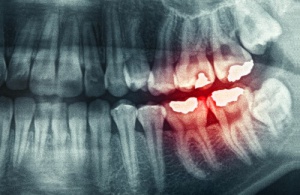

- Prematüre diş aşınması.

- Dişlerde çatlaklar.

- Diş minesinin kaybı.

- Dişlerde aşırı hassaslık